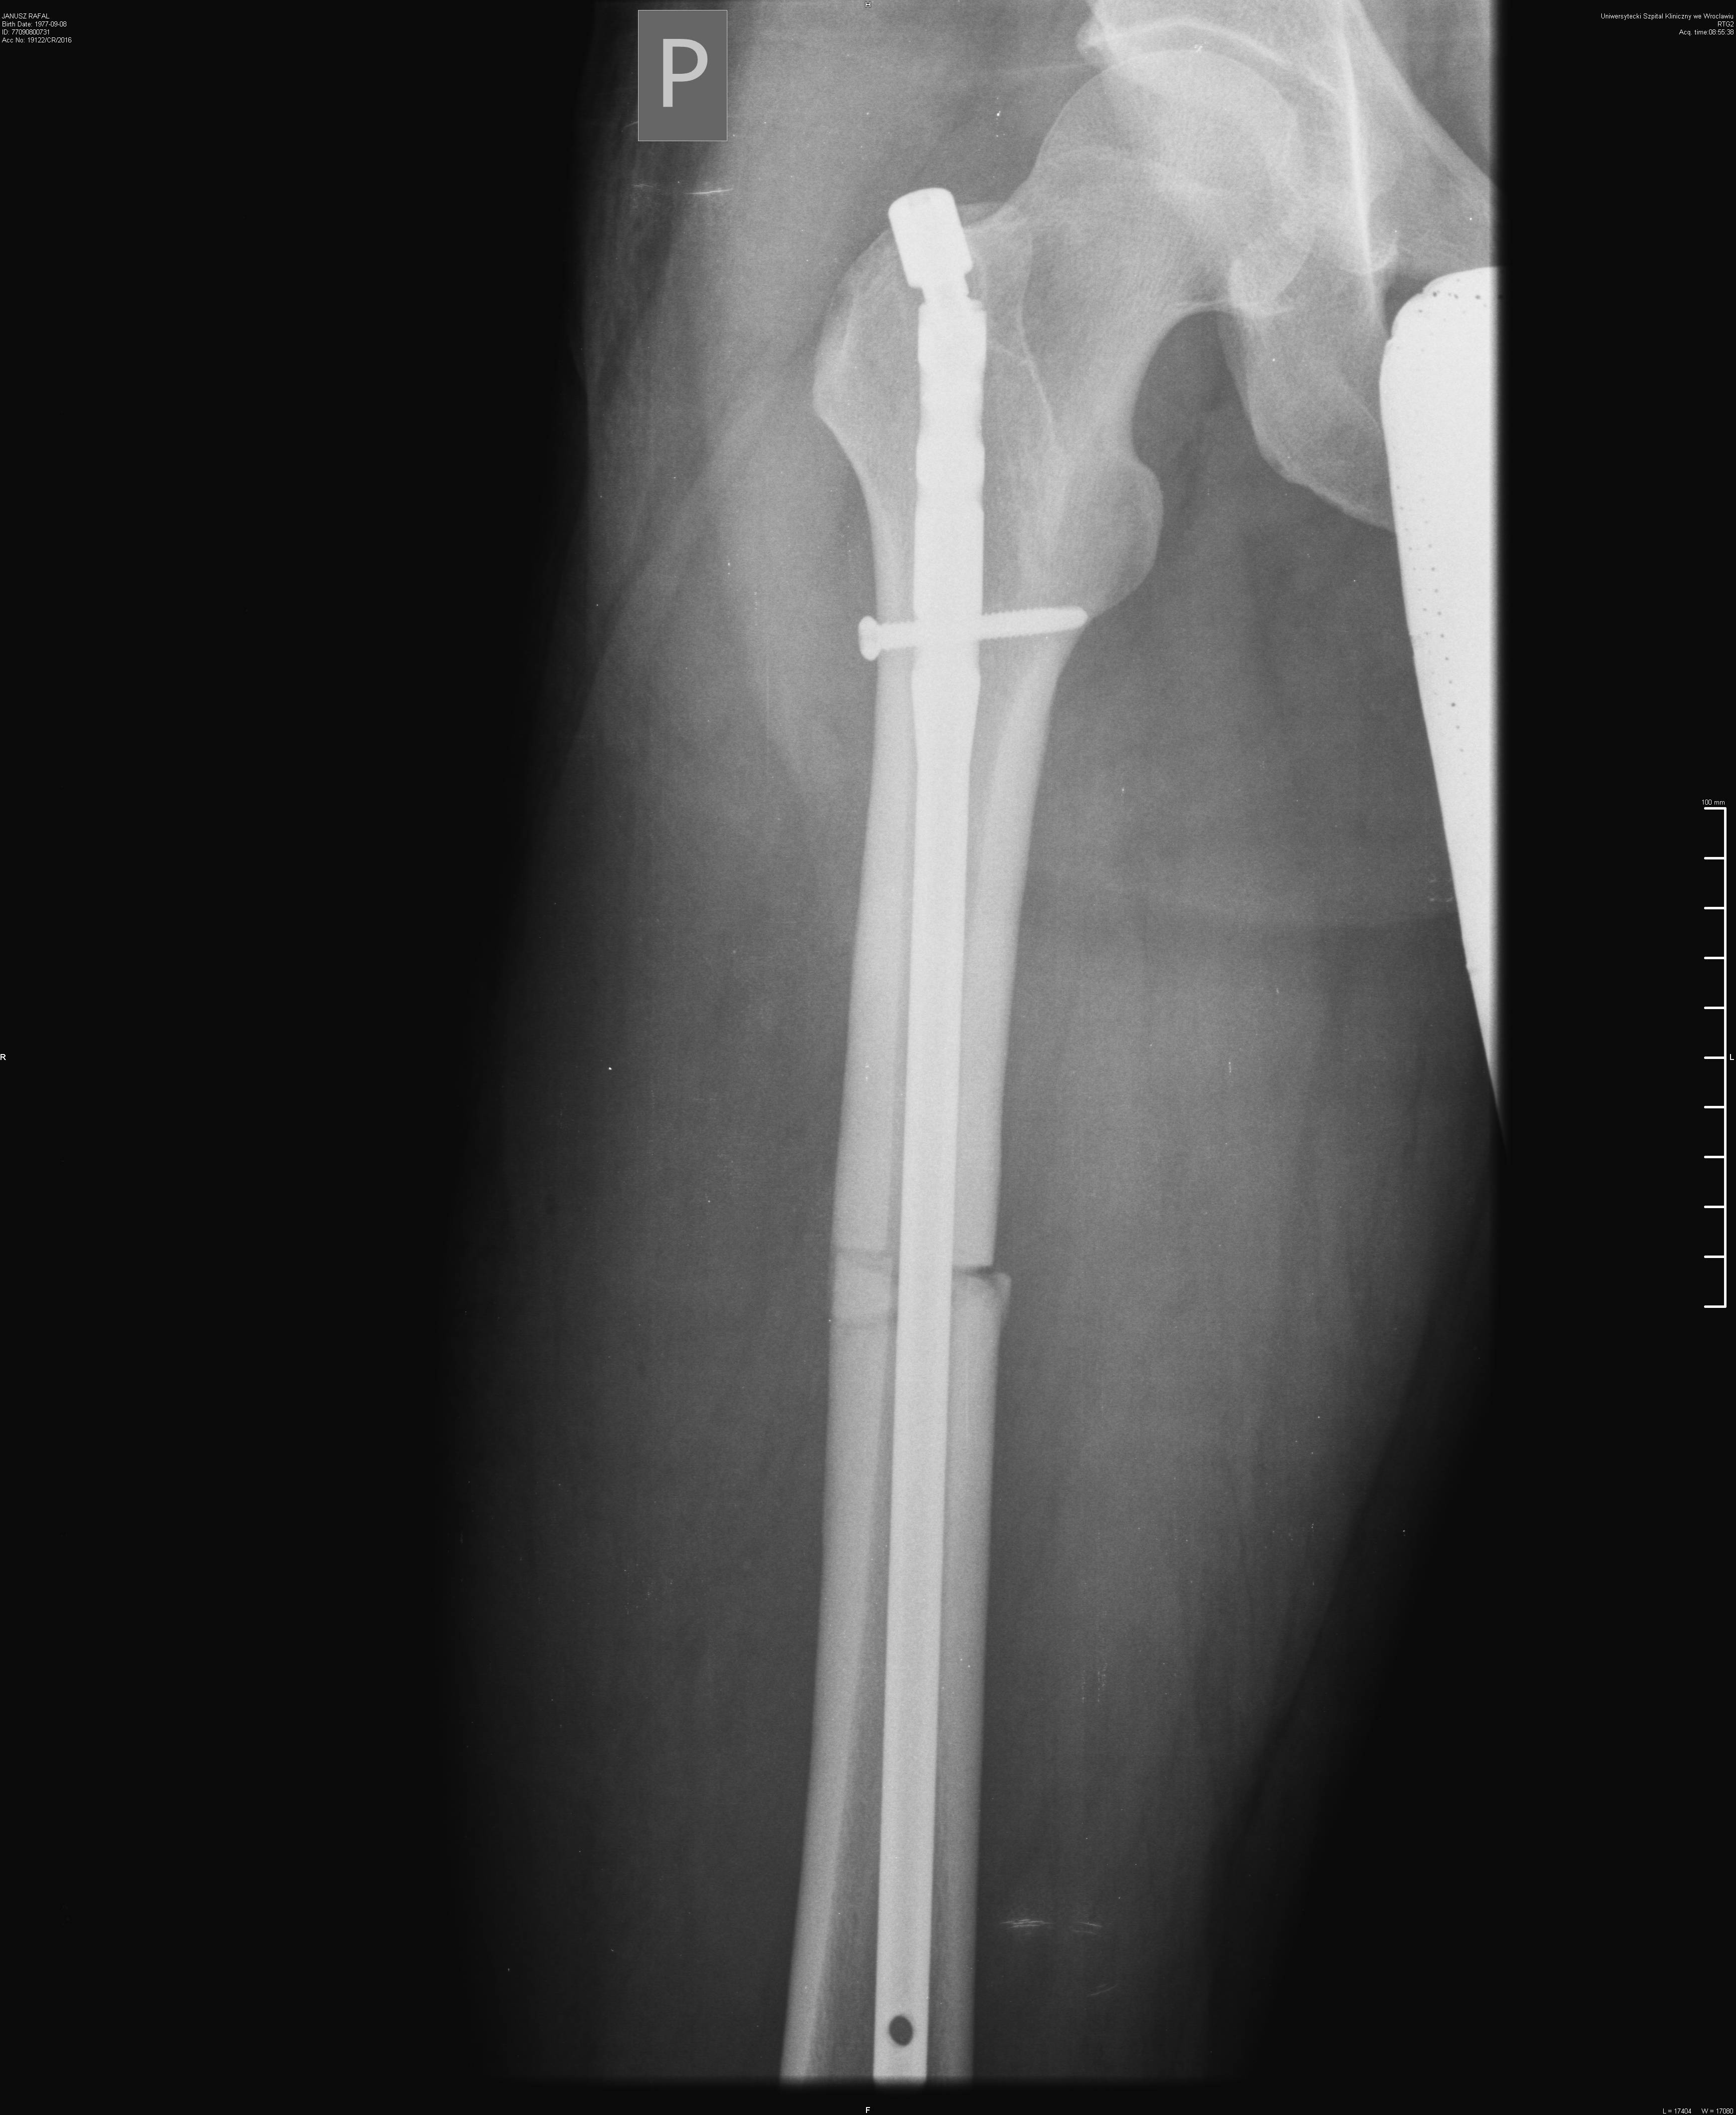

Przez blisko rok, tzn. od 11.05.2016 rower poszedł w odstawkę. Jednak doszedłem do wniosku, że taka kontuzja może zdarzyć się również w innych okolicznościach: